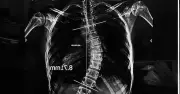

Đề xuấtNhiều gia đình sẵn sàng chi hàng trăm triệu đến cả tỷ đồng để điều trị cong vẹo cột sống cho con, một bệnh lý ngày càng phổ biến ở trẻ em và thanh thiếu niên.